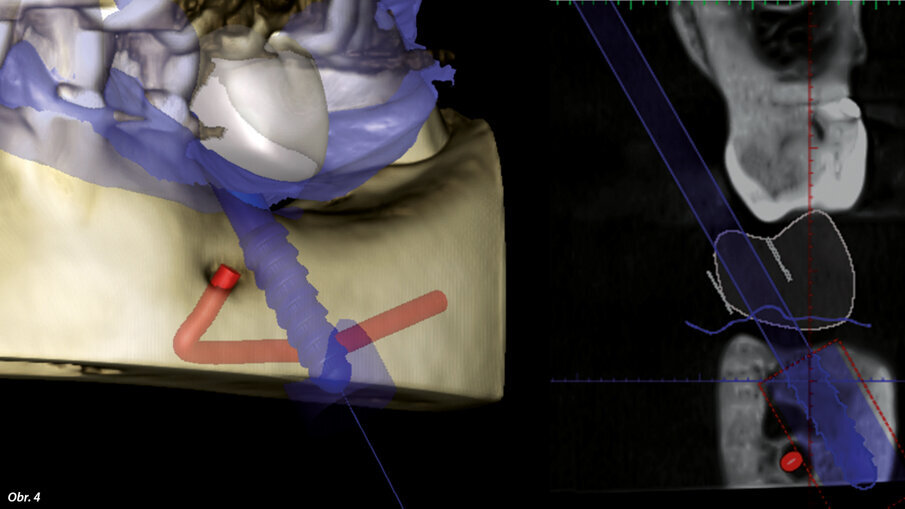

Na naše oddělení se dostavila pacientka, 52 let, s implantátem v místě 36, který byl zaveden na jiném pracovišti asi před 6 lety. Implantát vykazoval známky odhojení. Na OPG (ProMax, Planmeca) byl patrný velký úbytek kosti v okolí implantátu způsobený periimplantitidou (obr. 2). Proto byl implantát odstraněn, defekt byl exkochleován. Po 3 měsících bylo zhotovené CBCT (ProMax, Planmeca) pro plánování náhrady implantátu (obr. 3). Po zvážení všech možností (vertikální augmentace, short implant) jsme se rozhodli k zavedení tilted implantátu, který bude zaveden tak, aby míjel průběh mandibulárního kanálu (obr. 4). CBCT sken nám pomohl přesněji určit polohu mandibulárního kanálu. V programu jsem si následně vybral vhodný průměr i délku implantátu a určil jeho polohu tak, aby se vyhnul průběhu kanálu a zároveň respektoval aktuální nabídku kosti. Je velmi důležité podívat se na situaci z různých pohledů, abychom se ujistili, že jsme ošetření správně naplánovali.

Plánovaná pozice implantátu BioniQ v blízkosti mandibulárního kanálu.